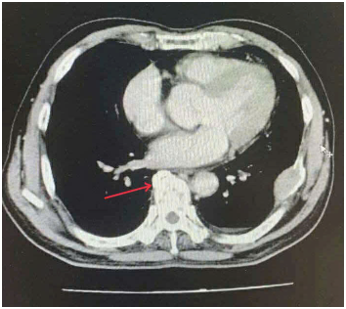

Ca lâm sàng:Hiệu quả điều trị đích bằng Osimertinib ở bệnh nhân UT biểu mô tuyến của phổi giai đoạn IV có đột biến gen EGFR L858R (Exon 21) tại Trung tâm YHHN&UB-Bệnh viện Bạch Mai

Ung thư phổi là một trong những ung thư có tỷ lệ mắc và tử vong cao nhất trên toàn thế giới. Theo GLOBOCAN 2022, ung thư phổi đứng thứ hai về số ca mắc mới với khoảng 2,5 triệu trường hợp mỗi năm và là nguyên nhân hàng đầu gây tử vong do...